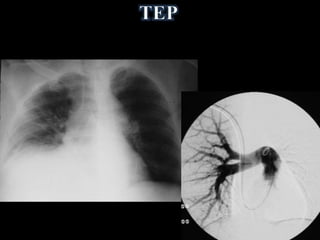

• Redução da

vascularização

(TEP, Swyer James)

• Redução da vascularização (TEP, Swyer James)

• Hiperinsuflação semdoença pulmonar • Hiperinsuflação com redução do tecido pulmonar • Redução da vascularização (TEP, Swyer James) • Combinados • Outros (pneumotórax, Polland)